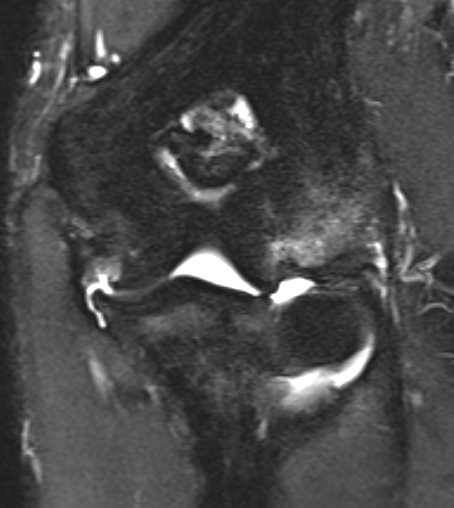

Bony avulsion UCL complex medial epicondyle

PRLIPLRI

Bony avulsion UCL sublime tubercle